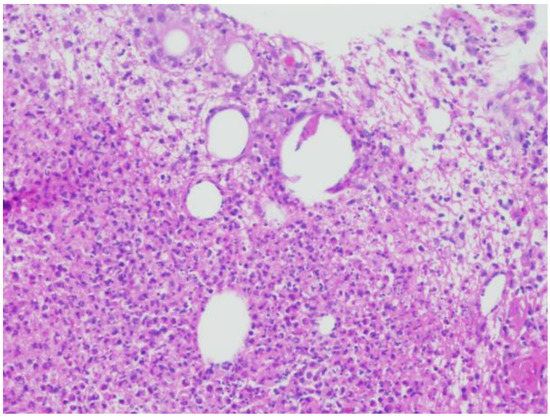

A 38-year-old female with Fitzpatrick type III skin presented to the dermatology clinic with a tender, warm, erythematous 5 cm plaque on the left breast. She was evaluated for both infectious and malignant processes with fine-needle aspiration, two-punch biopsies, and tissue culture. Histologically, her biopsies demonstrated numerous focally necrotic granulomata with negative fungal, acid-fast bacterial, and Gram stains (Figure 1) At that time, a diagnosis of CNGM was made. Treatment initially consisted of doxycycline 100 mg twice daily and oral prednisone. Despite prolonged courses of prednisone, her disease was not controlled with tapering to doses lower than 40 mg daily.

Figure 1. Hematoxylin and eosin staining at 20× magnification, showing cystic spaces with granulomatous inflammation and mixed neutrophilic and lymphohistiocytic inflammation.